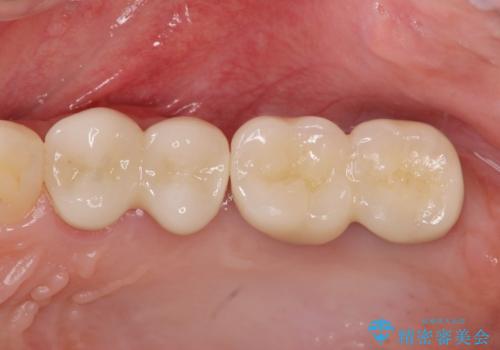

奥歯を2本失ったのち、しっかりと噛める環境へと整備するため、しっかりと骨の造成を行い清掃性を高めたインプラント治療を行っていくこととしました。

- 110万円(インプラント×2・チタンカスタムアバットメント×2・ジルコニアクラウン×2・仮歯×2・ 骨造成・サイナスリフト)費用は治療当時の料金となります

インプラントの仕上がりを見越して、ただ埋入するだけではなく長期的な予後を見込むには清掃のしやすい環境を整備することが大切です。

今回は大きく吸収してしまった歯槽骨をしっかりと造成することで、歯間ブラシを行いやすいインプラント周囲環境を整備することができました。